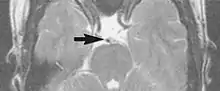

Flow can manifest as either an altered intravascular signal (flow enhancement or flow-related signal loss), or as flow-related artifacts (ghost images or spatial misregistration). Flow enhancement, also known as inflow effect, is caused by fully magnetised protons entering the imaged slice while the stationary protons have not fully regained their magnetization.[1] The fully magnetized protons yield a high signal in comparison with the rest of the surroundings. High velocity flow causes the protons entering the image to be removed from it by the time the 180-degree pulse is administered. The effect is that these protons do not contribute to the echo and are registered as a signal void or flow-related signal loss (Fig. 2).[1] Spatial misregistration manifests as displacement of an intravascular signal owing to position encoding of a voxel in the phase direction preceding frequency encoding by time TE/2.The intensity of the artifact is dependent on the signal intensity from the vessel, and is less apparent with increased TE.[1]